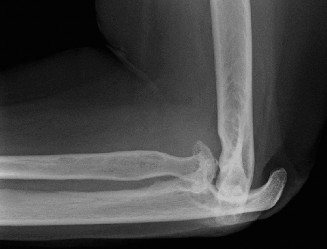

The patient undergoes a total shoulder arthroplasty via deltopectoral approach. At her 2-week postoperative visit, the incision is healing well and her pain is controlled with 1 to 2 tablets of hydrocodone-acetaminophen daily. You give her a prescription for physical therapy. Four weeks later, the patient returns to clinic complaining of an increase in shoulder pain as well as weakness for the past 3 days, especially when getting dressed. She does not recall any traumatic event. On examination her incision remains clean, dry, and intact; there is a positive finding of weakness when resistance is applied to the arm in an adducted and internally rotated position behind the back. X-rays are shown in Figure 2–51.

Figure 2–51

What is the most likely explanation?

The correct answer is (C). During the deltopectoral approach, the subscapularis tendon is detached from the anterior humerus so the humeral head may be exposed. The tendon is reattached after placement of the components, and there is a postoperative risk of repair failure, especially during rehabilitation. Precautions to avoid in rehabilitation include limiting external rotation of the shoulder and avoiding such movements as pushing out of a chair. Pendulum exercises and passive range of motion supervised by physical therapy are advised, and active range of motion of the elbow, wrist, and hand should be encouraged to avoid stiffness. Choice “A” is incorrect because the patient’s symptoms are more consistent with subscapularis tear, and there is no radiographic evidence of loosening. Choice “B” is incorrect because infection is more associated with loosening. Choice “D” is incorrect because axillary nerve palsy would likely present as weakness with shoulder abduction and/or sensory changes in the skin around the deltoid. Objectives: Did you learn...? Recognize the clinical presentation of glenohumeral osteoarthritis? Treat a patient with glenohumeral osteoarthritis?